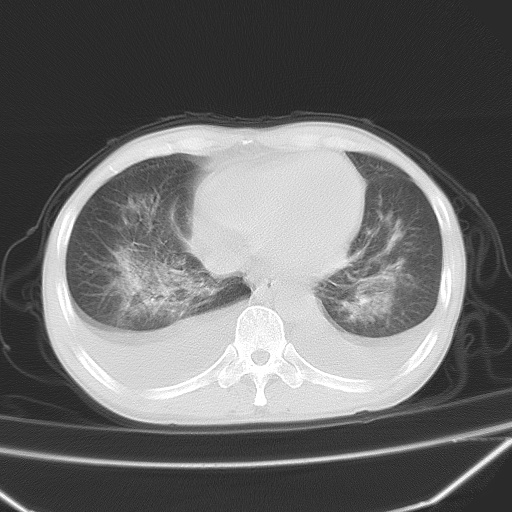

男、42岁、咯血3天。既往有甲亢、贫血、血尿蛋白尿史多年。血象:wbc:6.   中性粒:70.6%。

双肺野对称性磨玻璃影,分布于内中带,双侧胸水,患者有咯血。

双肺野广泛对称性磨玻璃影、实变影,以肺门为中心,主要分布于内中带,符合典型肺泡性肺水肿;伴双侧胸腔少量游离积液。结合患者既往病史且咯血就诊,支持多因素(尿毒症等)所致之肺水肿、肺出血、胸水;影像表现暂不考虑心源性水肿,且症状也不太符。需密切随诊结合临床治疗等进一步明确。